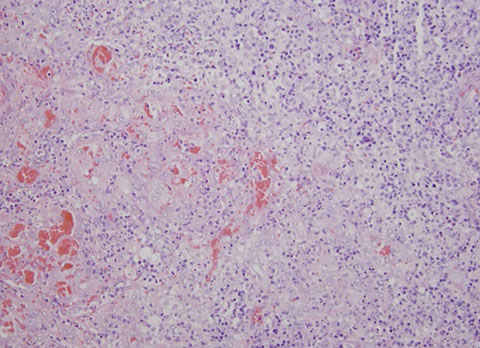

Syphalitic lymphadenitis [3]. Florid follicular hyperplasia with back-to-back appearance with little paracortex (may raise suspicion for malignancy), although the follicles have some degree of polarization. The capsule is intact, and appears thickened. There is some variability in the size and shape of the follicles (though that is a soft sign because can be seen in some low-grade follicular lymphomas). Plasma cells in the follicles in reactive GCs and in the thickened capsule.

Syphilis can have marked plasmacytosis, which is polytypic, can even have high IgG4 to IgG ratio, but IHC should reveal the organisms [3]

Syphilis. Areas with markedly-expanded paracortex with mix of lymphocytes, histiocytes, neutrophils, and sclerosis.